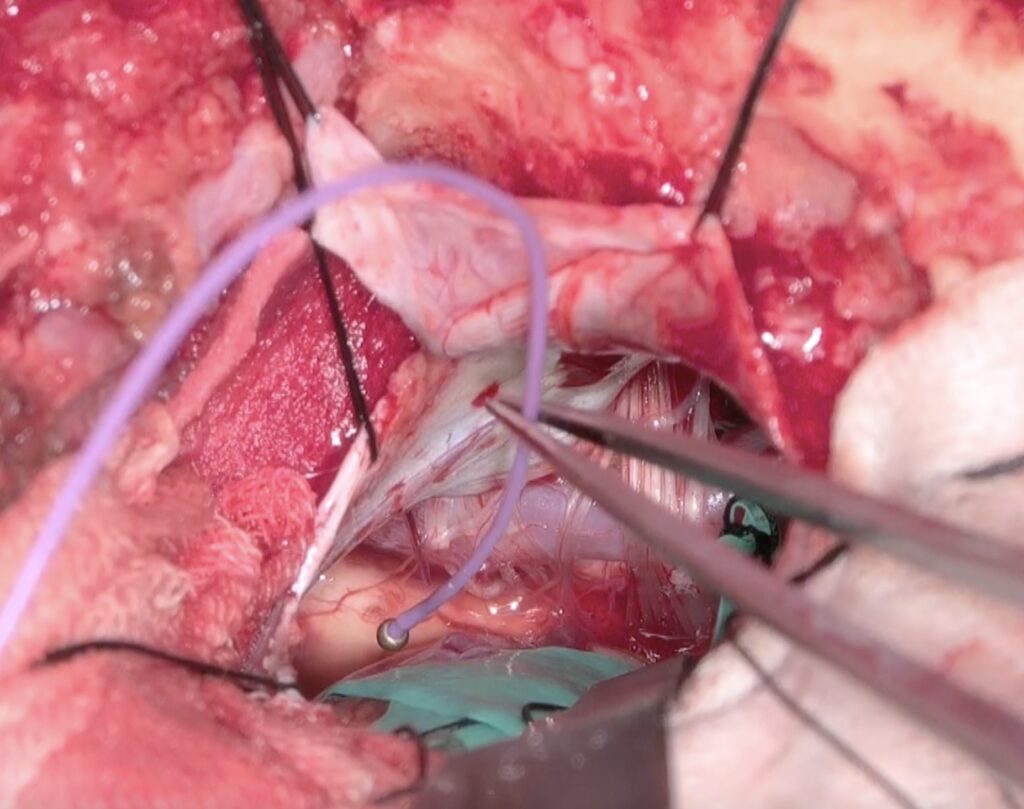

VAが脳神経を引き伸ばしており、M-TEPを用いて延髄虚血をモニタリングし、Wallenbergの発生を予防しました。少しの小脳牽引で迷走神経反射が生じたり、ABRが低下したりしたが、少しずつやっていくことでうまく徐圧できました。特に後遺症なく、痙攣は消失しました。